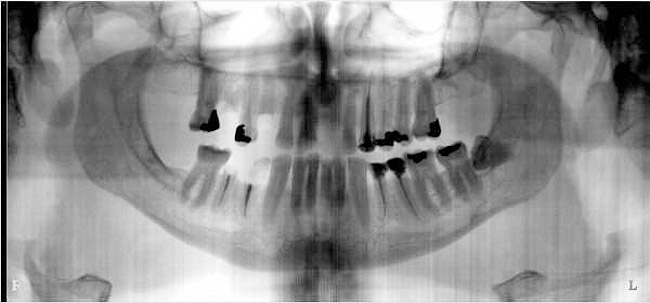

Figure 1  The crown height is measured from the alveolar crest to the occlusal table.

Figure 1

Figure 10a  Supra-eruption of the opposing arch, thus diminishing crown height space.

Figure 10a

Figure 10b  Supra-eruption of the opposing arch, thus diminishing crown height space.

Figure 10b